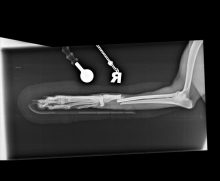

Pantarsal arthrodesis in a cat due to a chronic tarsal instability

By Eastcott Referrals Orthopaedic Surgeon Fabio Frazzica A 6-year-old female domestic short-haired cat was referred to us with a ...